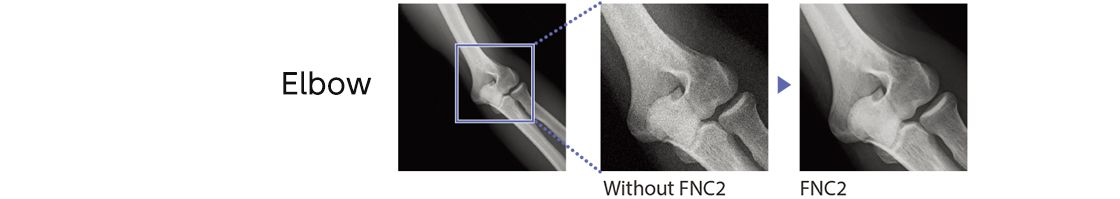

suppressing complex noise components from the image

FNC2 extracts the noise component in the image by recognizing complex line and dot components as well as estimating the noise amount in relation to body thickness.